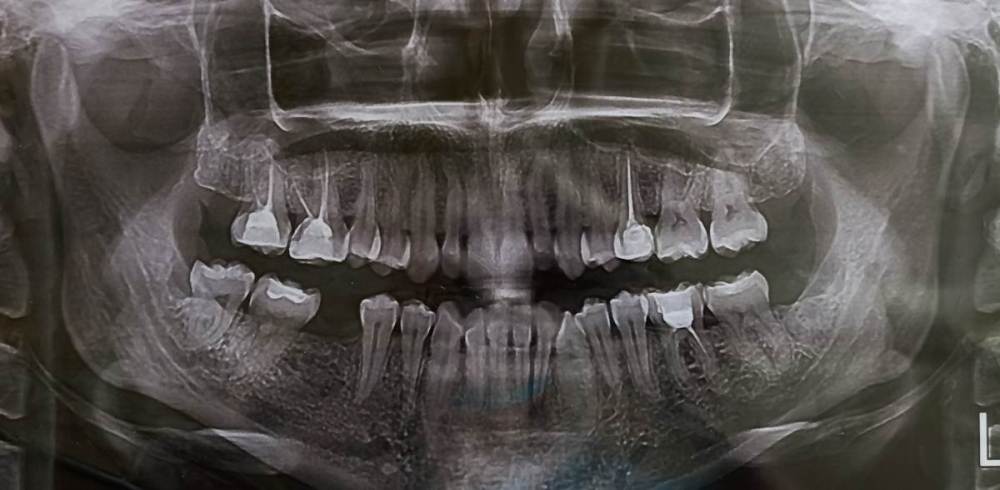

Mariaduya Опубликовано 5 июля, 2023 Поделиться Опубликовано 5 июля, 2023 (изменено) Здравствуйте. У меня сложная ситуация, боли в челюсти практически 1.5 года. Врачи не видят проблем, уже не знаю куда обратиться. Хронология. 1. В ноябре 2021 начал слегка болеть 1.6 зуб. В стоматологии мне его сразу начали депульпировать, без снимка. В ходе лечения не болел, как запломбировали каналы, постепенно появилась ноющая, постоянная боль. Я обратилась снова, сказали, что на зубе есть хроническое воспаление и ввели антибиотик туда при помощи электрофареза. Среагировал 2.5 зуб с другой стороны, и тоже начал постоянно болеть, он был депульпирован давно, но в нем развился большой кариес. 2. Мне начали их перелечивать. 1.6. не получилось пройти канал, залили резодентом, 2.5 просто переличили. 3. Боль все ещё осталась, уже в двух зубах. Врачи ничего не знают, отправили к неврологу, ЛОРУ и т.д. 4. Обошла неврологов, лоров, делала мрт, кт с контрастом головы, пазух носа, все ок. Невролог выписывает финлепсин, не помог. 5. Делала в частной клинике кт зубов, без описания, ещё не знала, что оно нужно, врач посмотрела и сказала, что видит небольшое, хроническое воспаление на 1.6 зубе и все, а так она не знает. 6. И так 1.5 года никто не знает, что со мной. Боль 1.6 и 2.5 зубы, начинают и нижние зубы болеть, уже и ухо болит. После орви болит все очень сильно, что хочется уже не просыпаться. Удалять их говорят не показаний, вдруг боль останется. Снимки в хронологии выкладываю. Есть ли на них воспаление 1.6 зуба, 2.5 зубов, есть ли них кисты свищи и все что угодно, что аномально и может вызывать боль. Может что-то с надкостницой, или суставами. Все что у меня есть - интернет, так как живу я очень далеко от нормального города и доступна только городская поликлиника, где врачи говорят, что это неврология, а невролог говорит наоборот. Сами зубы болят странно, по очереди. Если болит неделю 1.6 зуб, то 2.5 не болит и так наоборот. Вместе они не болят. Ещё странное то, что они практически симметричны друг другу по расположению. Изменено 5 июля, 2023 пользователем Mariaduya Ссылка на комментарий

Carioznik Опубликовано 5 июля, 2023 Поделиться Опубликовано 5 июля, 2023 Здравствуйте, 27 зуб надо внимательнее посмотреть, возможно там пульпит (но это неточно "бумажные " снимки малоинформативны). Скиньте лучше КТ или хотя бы ОПТГ но в электронном формате(а не фото распечатки на бумаге) Ссылка на комментарий

Mariaduya Опубликовано 8 июля, 2023 Автор Поделиться Опубликовано 8 июля, 2023 Все, что у меня есть мне давали в распечатке и я фотографировала на сотовый, есть ещё одна оптг более лучшего качества, сделана год назад. КТ сделано в самом начале, в декабре 2021. 925191586_.iso Ссылка на комментарий

Mariaduya Опубликовано 8 июля, 2023 Автор Поделиться Опубликовано 8 июля, 2023 Уже после лечения 25 и 16 зубов, он отличается от современного только тем, что перелечивали ещё нижний 6 зуб. А так, такая же ситуация, как и на сегодня. Ссылка на комментарий

Carioznik Опубликовано 13 июля, 2023 Поделиться Опубликовано 13 июля, 2023 по этому старому КТ: на 16 - есть пропущенный канал, от этого, на одном из корней - есть небольшой воспалительный процесс (на тот момент). "Само не заживет", будет только расти, может, на сегодняшний момент - уже стал большой). Но жалобы в таких случаях обычно другие. Делайте новое КТ (по старому только гадать...) и снова, очный осмотр стоматолога, явно понадобится. 1 Ссылка на комментарий